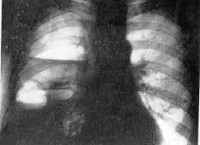

Рентгенограмма при пиопневмотораксе характеризуется смещением органов средостения в здоровую сторону, наличием одного или нескольких горизонтальных уровней жидкости (гноя) в полости плевры, над которыми определяется резко выделяющийся воздушный пузырь. При неограниченном пиопневмотораксе наблюдается частичное или полное спадение легкого, при ограниченном процессе - вытянутые веретенообразные осумкованные гнойно-воздушные полости. Разделение листков висцеральной и париетальной плевры патогномонично для пиопневмоторакса и хорошо определяется при плеврографии после контрастного усиления.